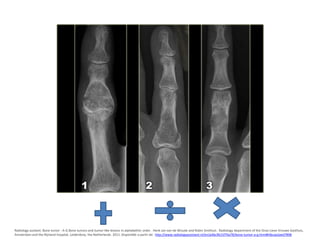

Radiology assitant. Bone tumor - A-G Bone tumors and tumor-like lesions in alphabethic order . Henk Jan van de Woude and Robin Smithuis . Radiology

department of the Onze Lieve Vrouwe Gasthuis, Amsterdam and the Rijnland hospital, Leiderdorp, the Netherlands. 2011. Disponible a partir de:

http://www.radiologyassistant.nl/en/p4bc9b15f76a78/bone-tumor-a-g.html#i4bcaa2aed7898

Condroma

• Tumor benigno caracterizado por la formación

de cartílago maduro.

• Puede ser central (encondroma) o periférico.

• Características clínicas

– Son asintomáticos

– Se DX luego de una fractura patológica o al tomar RX por

• Diagnostico por imágenes.

– Lesión metafisiaria o diafisiaria lítica, radiolucida,

expansiva, con calcificaciones moteadas en su interior.